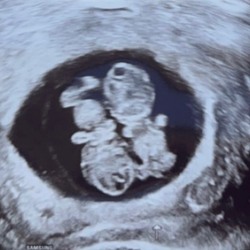

Ik voeg me graag bij deze groep. Afgelopen vrijdag is onze dochter geboren met precies 34 weken, na een keizersnede vanwege placenta-insufficiëntie. Gelukkig hebben de longrijpingsinjecties goed hun werk gedaan en heeft ze een mooie start kunnen maken.

Behalve dat ze prematuur is, is ze ook dysmatuur. We zijn intens dankbaar en gelukkig dat ze er is — klein, maar krachtig. Tegelijkertijd is het ook een pittige en onzekere tijd. Ik weet nog niet hoe de komende weken eruit zullen zien, maar samen met haar papa en grote broer gaan we er alles aan doen om er het beste van te maken.

Ik sluit me graag aan! 2 mei is ons dochtertje geboren met 35+5. Ze woog 1604 gram en was 41,5cm (Dysmatuur en Prematuur)

ik sluit me ook aan bij deze groep😊 op 25 april 2024 ben ik bevallen van onze prachtige dochter op een termijn van 29 weken precies doormiddel van een acuut hellp syndroom en eclampsie. ze was 35 cm lang en woog 1175 gram! Ze is geboren in Hongarije en hebben een hele reis achter de rug gehad.